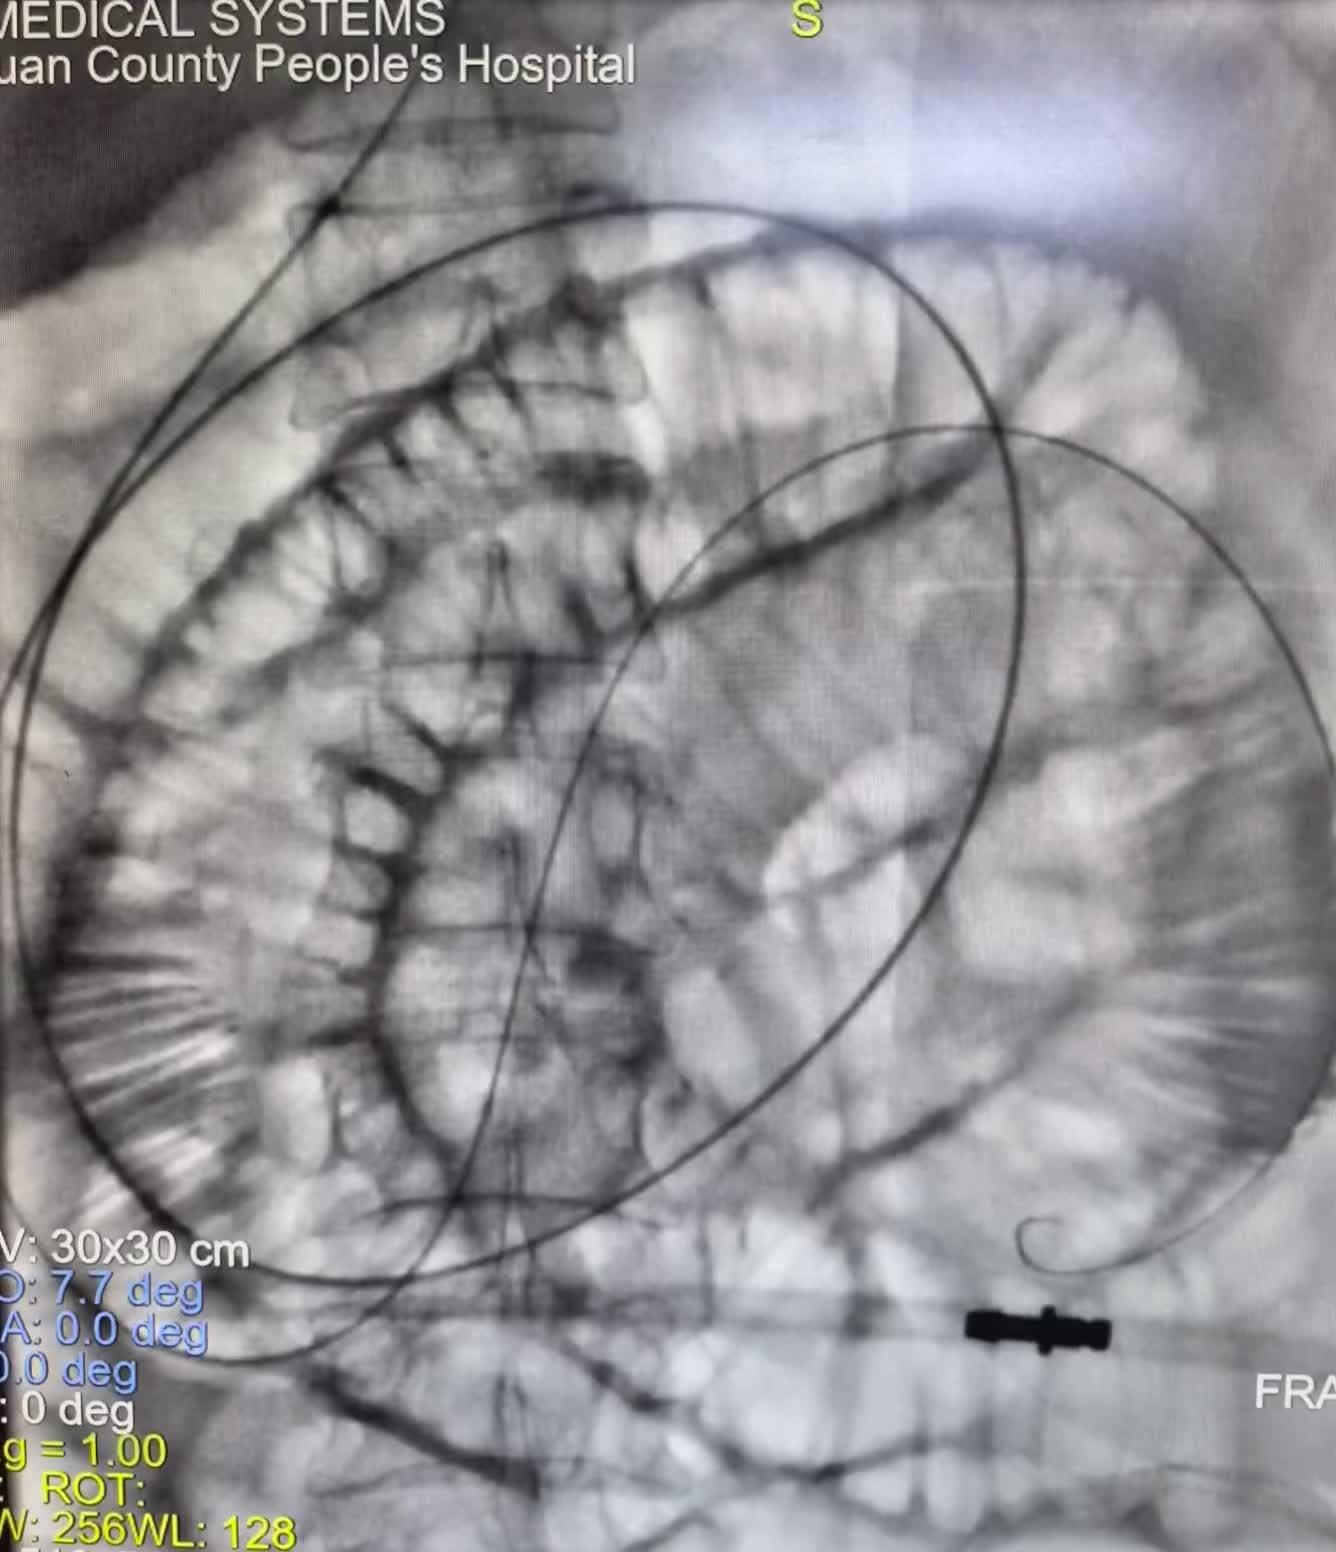

下午第一台糖尿病足三次腔内治疗再次未规律服药再次狭窄闭塞,下肢溃烂发黑...